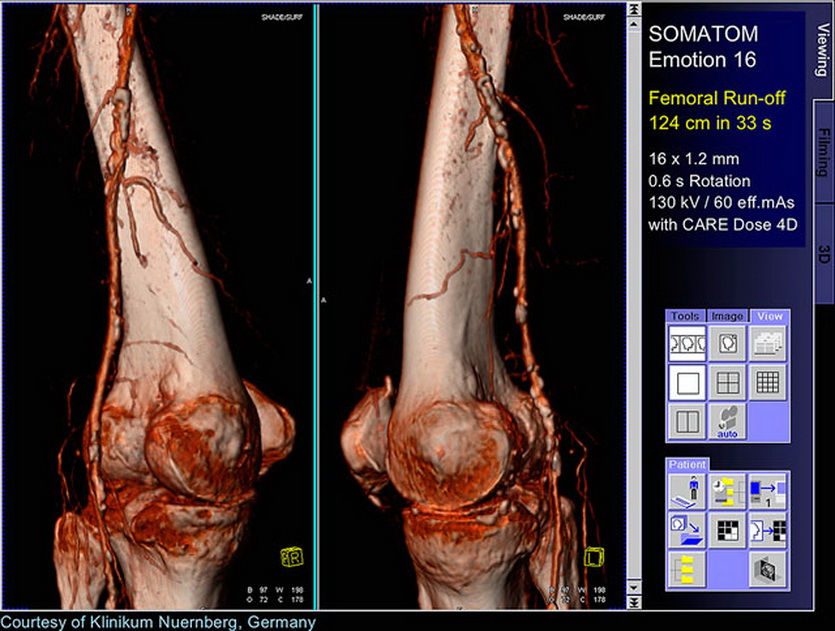

Томография позволяет строить сложные трехмерные модели

Если аномалия на рентгене может спрятаться за чем-то другим, поглощающим рентгеновское излучение лучше (так «исчезают» за костями многие опухоли), от КТ ей не убежать: специалист может повернуть изображение нужной стороной.

Точно так же с помощью трехмерного изображения оценивают состояние сложных поверхностей, практически неидентифицируемых на рентгене. Например, не только размеры, но и форму органов со всех сторон.

Кровеносную систему в динамике иначе не увидеть

Для обследования мягких тканей, которые сливаются на рентгеновских снимках с соседними, используют контрастную подсветку — йодосодержащие препараты, светящиеся в рентгеновском спектре.

Их вводят в орган или систему, которые после проявляются на томограмме. Например, с помощью инъекции в вену можно подсветить кровеносную систему, а выпитый индикатор проявляет желудочно-кишечный тракт.